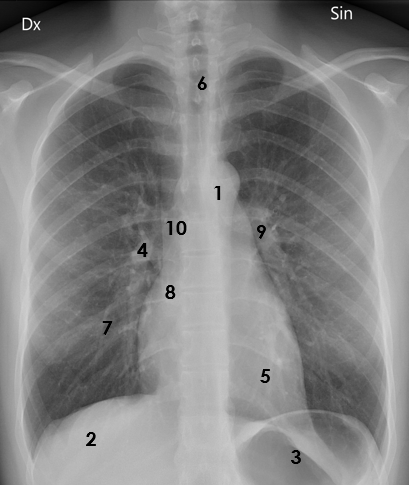

¿Te atreves a identificar las estructuras?

Fuente: Wiki – Dominio Público - Modificada por el autor